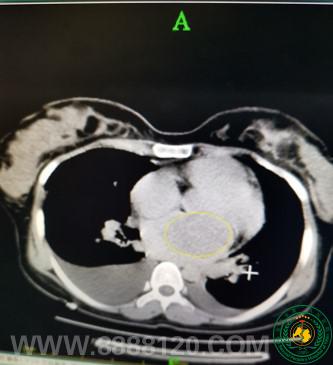

宜宾二医院胸心外科紧急抢修“心脏”发动机成功挽救一名急危重症患者

宜宾二医院胸心外科紧急抢修“心脏”发动机成功挽救一名急危重症患者27291